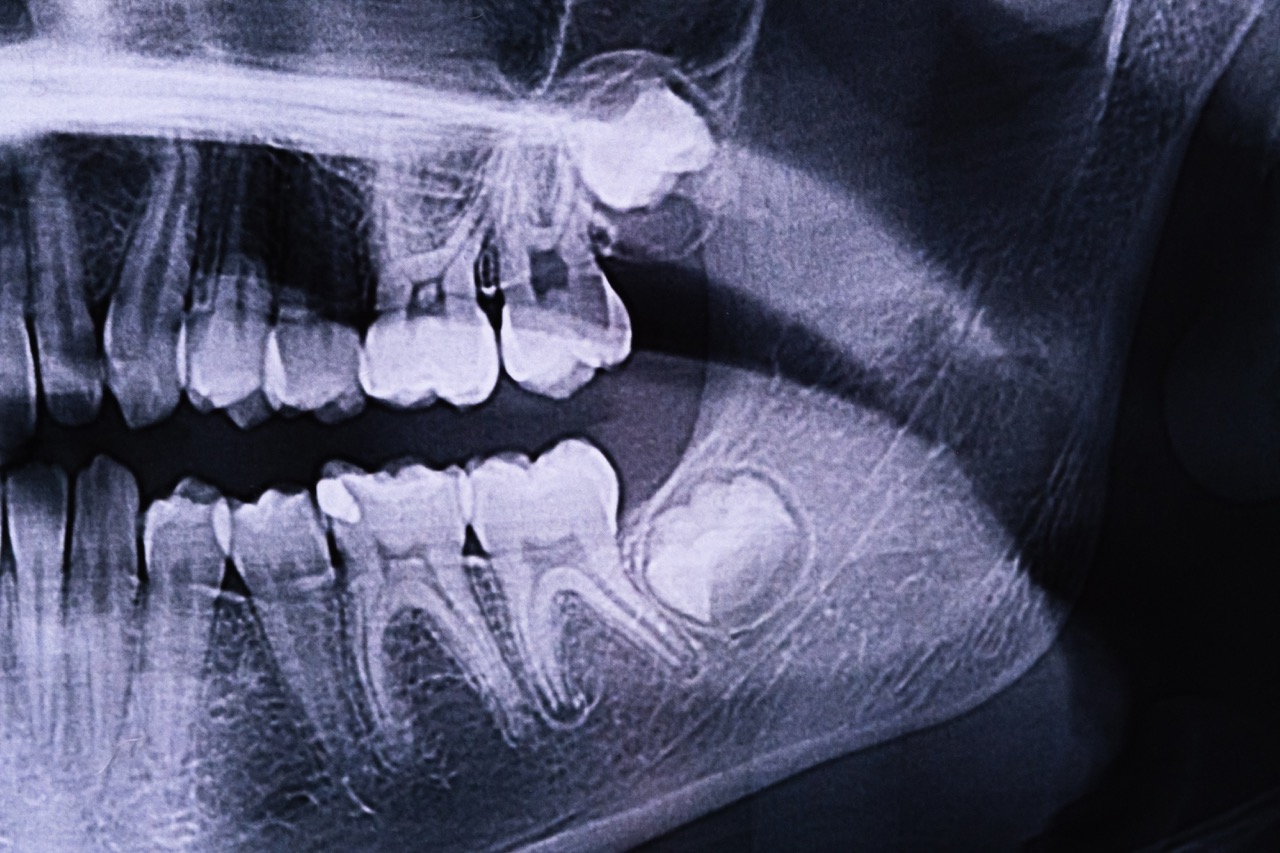

Digital X-Rays

Because our practice is dedicated to providing you with the safest and most convenient treatment options available, we utilize advanced digital X-ray technology in our office. Digital X-rays provide several advanced imaging options designed to shorten appointment times, provide clearer dental photos, and expose patients to less radiation than traditional X-ray technology. This also allows for easier communication when we refer you to a specialist, as we can easily transfer your images without loss of quality.

Panoramic X-ray of the jaw. X-ray of the teeth of a 12-year-old girl.